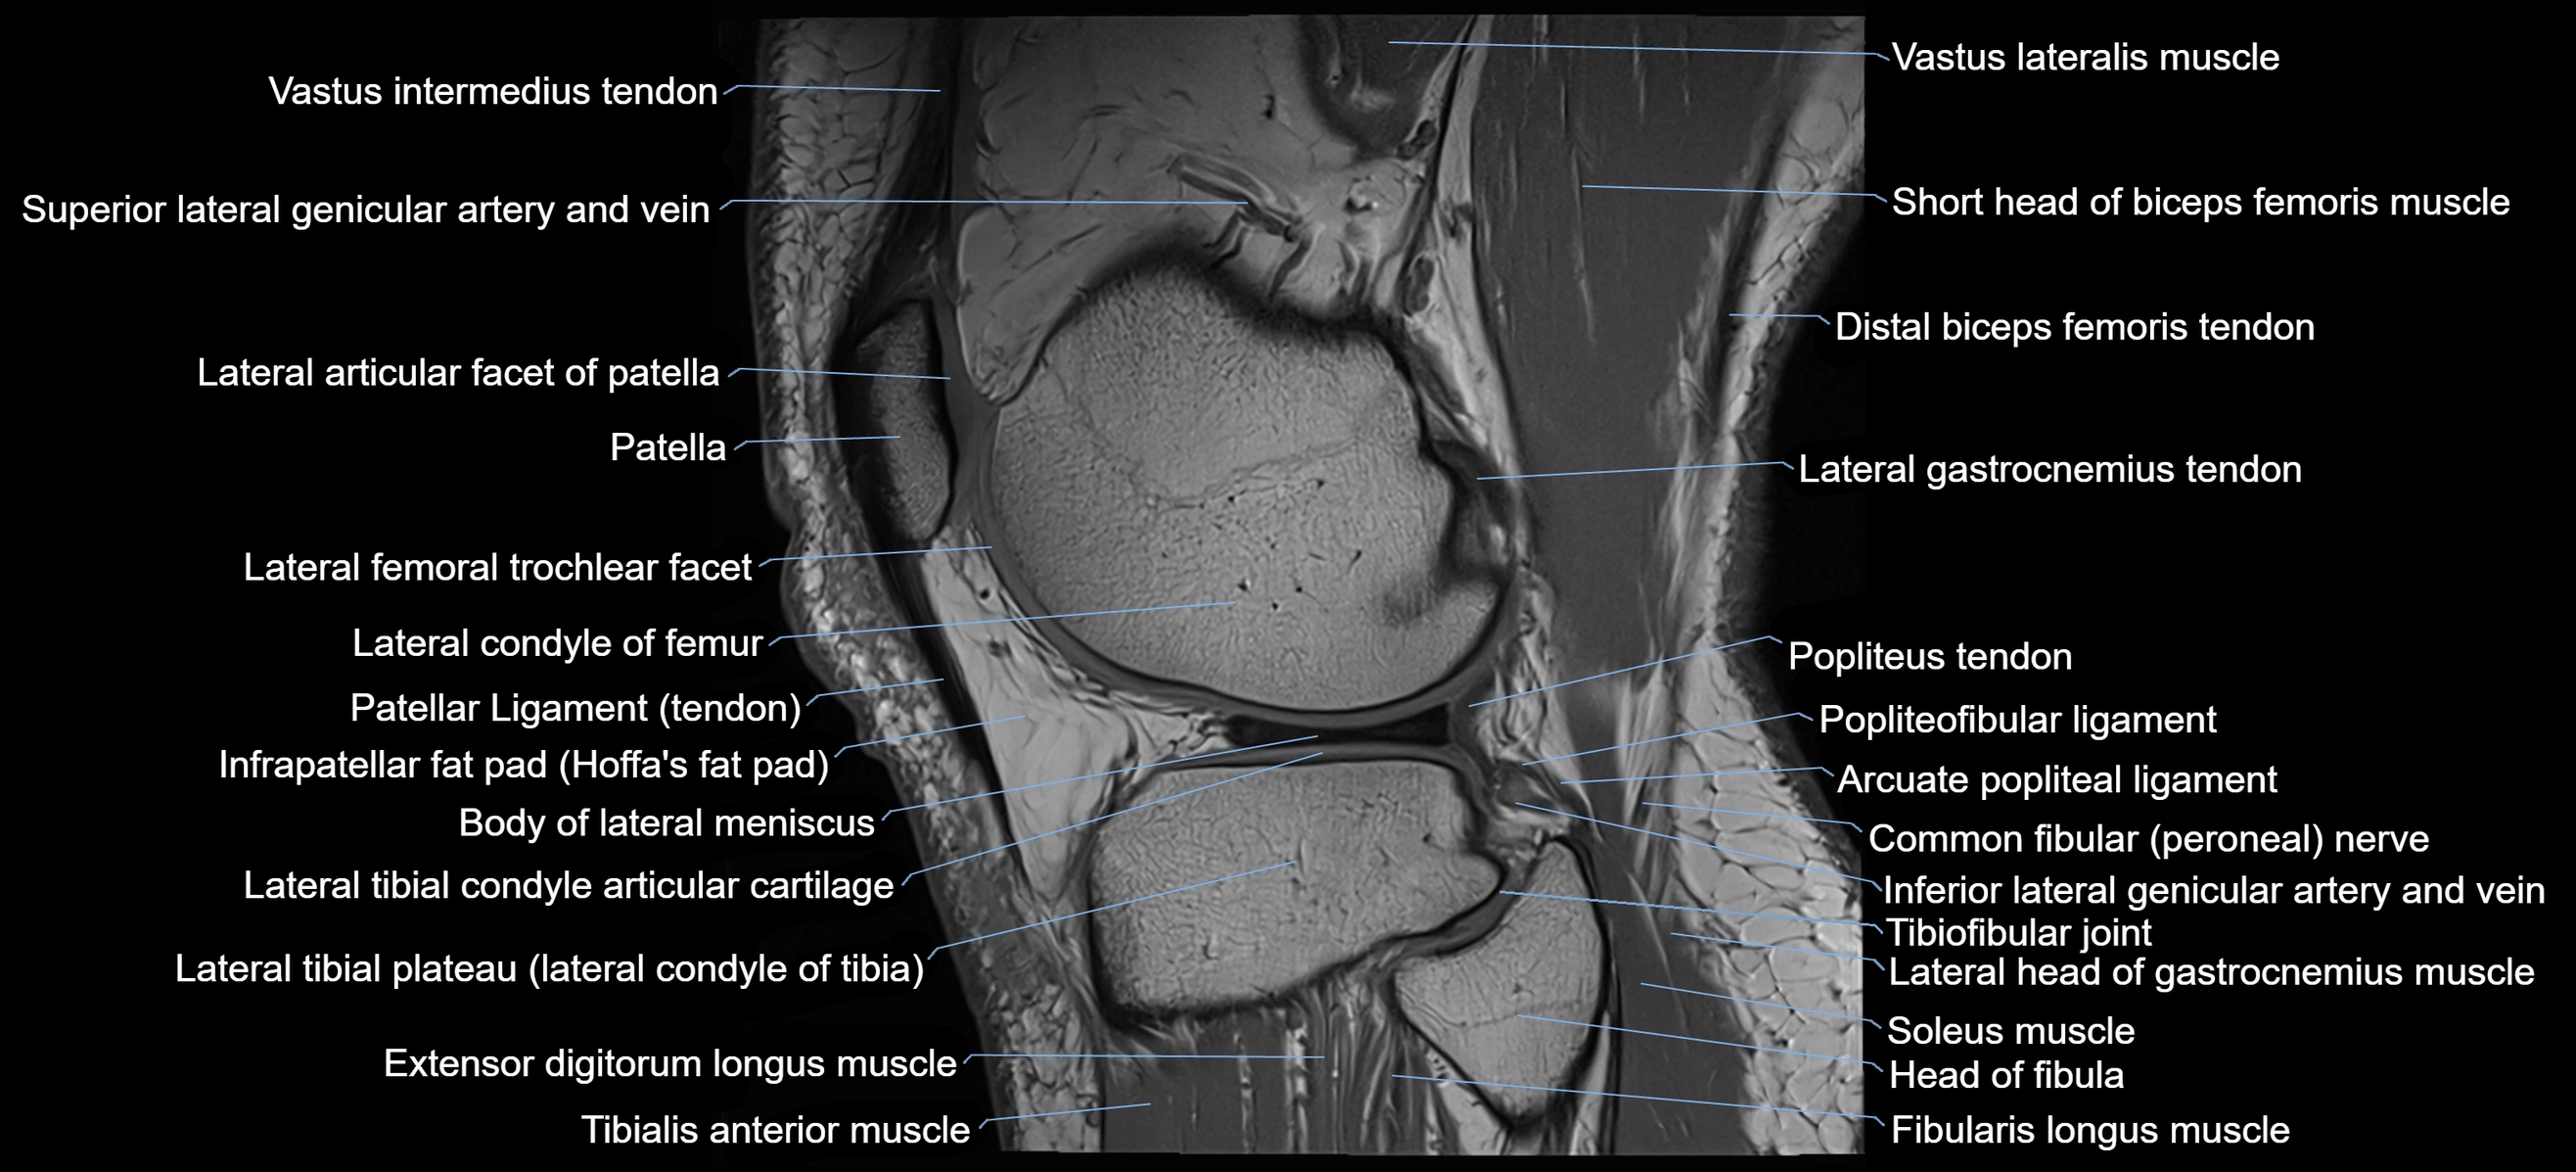

- Body of lateral meniscus

- Lateral articular facet of patella

- Lateral condyle of femur

- Lateral gastrocnemius tendon

- Lateral head of gastrocnemius muscle

- Lateral tibial plateau

- Patellar tendon (patellar ligament)

- Infrapatellar fat pad